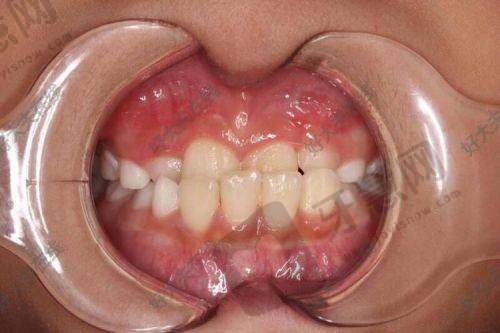

七、北京欢乐菲凡口腔门诊部顾客实例

北京欢乐菲凡口腔门诊部在当地口碑良好,众多患者对服务和治疗成效高度评价。以下是两则顾客实例评价:

顾客A:“我之前牙齿排列不整齐,想矫正又怕影响美观。到欢乐菲凡口腔门诊部后,医生推荐隐形正畸方案。矫正过程舒适,几乎感觉不到矫治器。医生和护士耐心,每次复诊详细沟通牙齿情况。现在牙齿整齐美观,感谢他们。”

顾客B:“我因牙齿缺失来做种植牙,医生技术不错,种植过程顺利,术后修复快。现在种植牙跟真牙一样,咀嚼功能修复好。门诊部环境干净整洁,服务周到,以后看牙就选这里。”